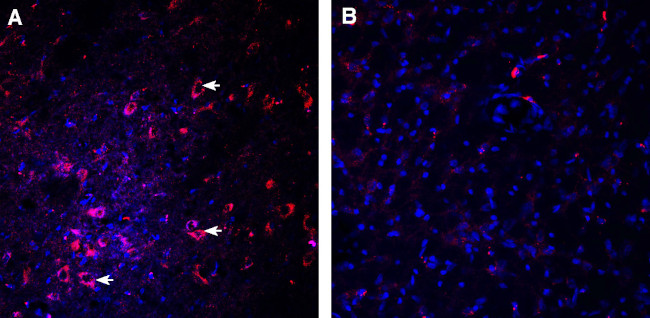

Dopamine Transporter (DAT) (extracellular) Antibody (AMT-003-GP-200UL) in IHC (F)

The Dopamine Transporter (DAT) is responsible for the reaccumulation of dopamine after it has been released. DAT antibodies and antibodies for other markers of catecholamine biosynthesis are widely used as markers for dopaminergic and noradrenergic neurons in a variety of applications including depression, schizophrenia, Parkinson's disease and drug abuse.